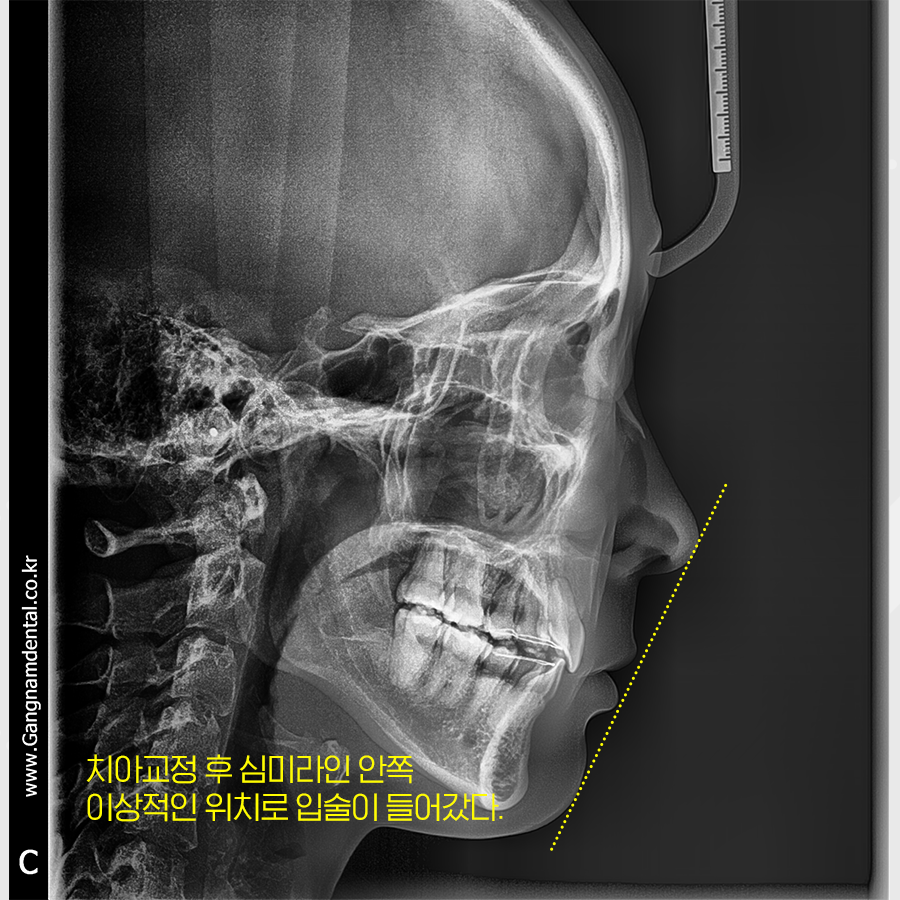

전치부 치아를 전체적으로 뒤로 이동하며

중절치의 각도를 조정했습니다.

옆모습만 보더라도 돌출입이

상당히 많이 들어간 모습을 확인할 수 있죠?

확실히 처음에 오셨을 때보다

더욱 활짝 웃으셨고

자신감도 부쩍 늘어난 듯 보였어요.